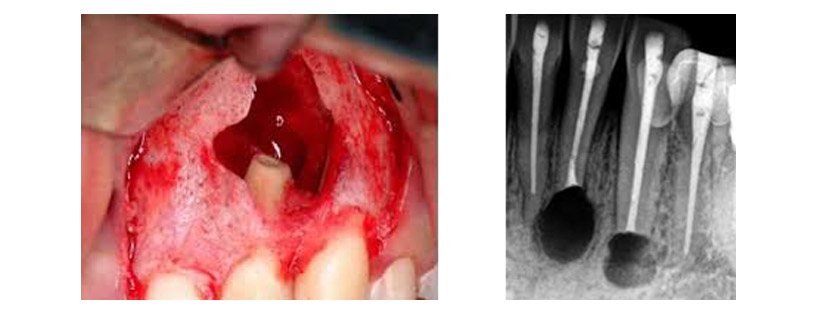

Ακροριζεκτομή

Είναι μία τεχνική που χρησιμοποιείται κατά τη χειρουργική ενδοδοντολογία, κατά την οποία, εκτός από την αφαίρεση των παθολογικών περιακροριζικών ιστών, αποκόπτεται και αφαιρείται τμήμα του άκρου της ρίζας του δοντιού περίπου δύο με τρία χιλιοστά το οποίο στη συνέχεια εμφράσσεται με ειδικά βιοσυμβατά υλικά. Συνήθως εκτελείται μετά από μία αποτυχημένη ενδοδοντική θεραπεία και εφόσον η φύση των προβλημάτων που προκάλεσαν τις επιπλοκές της αρχικής ενδοδοντικής θεραπείας δείχνουν ότι η επανάληψη της δε θα είναι επιτυχής.